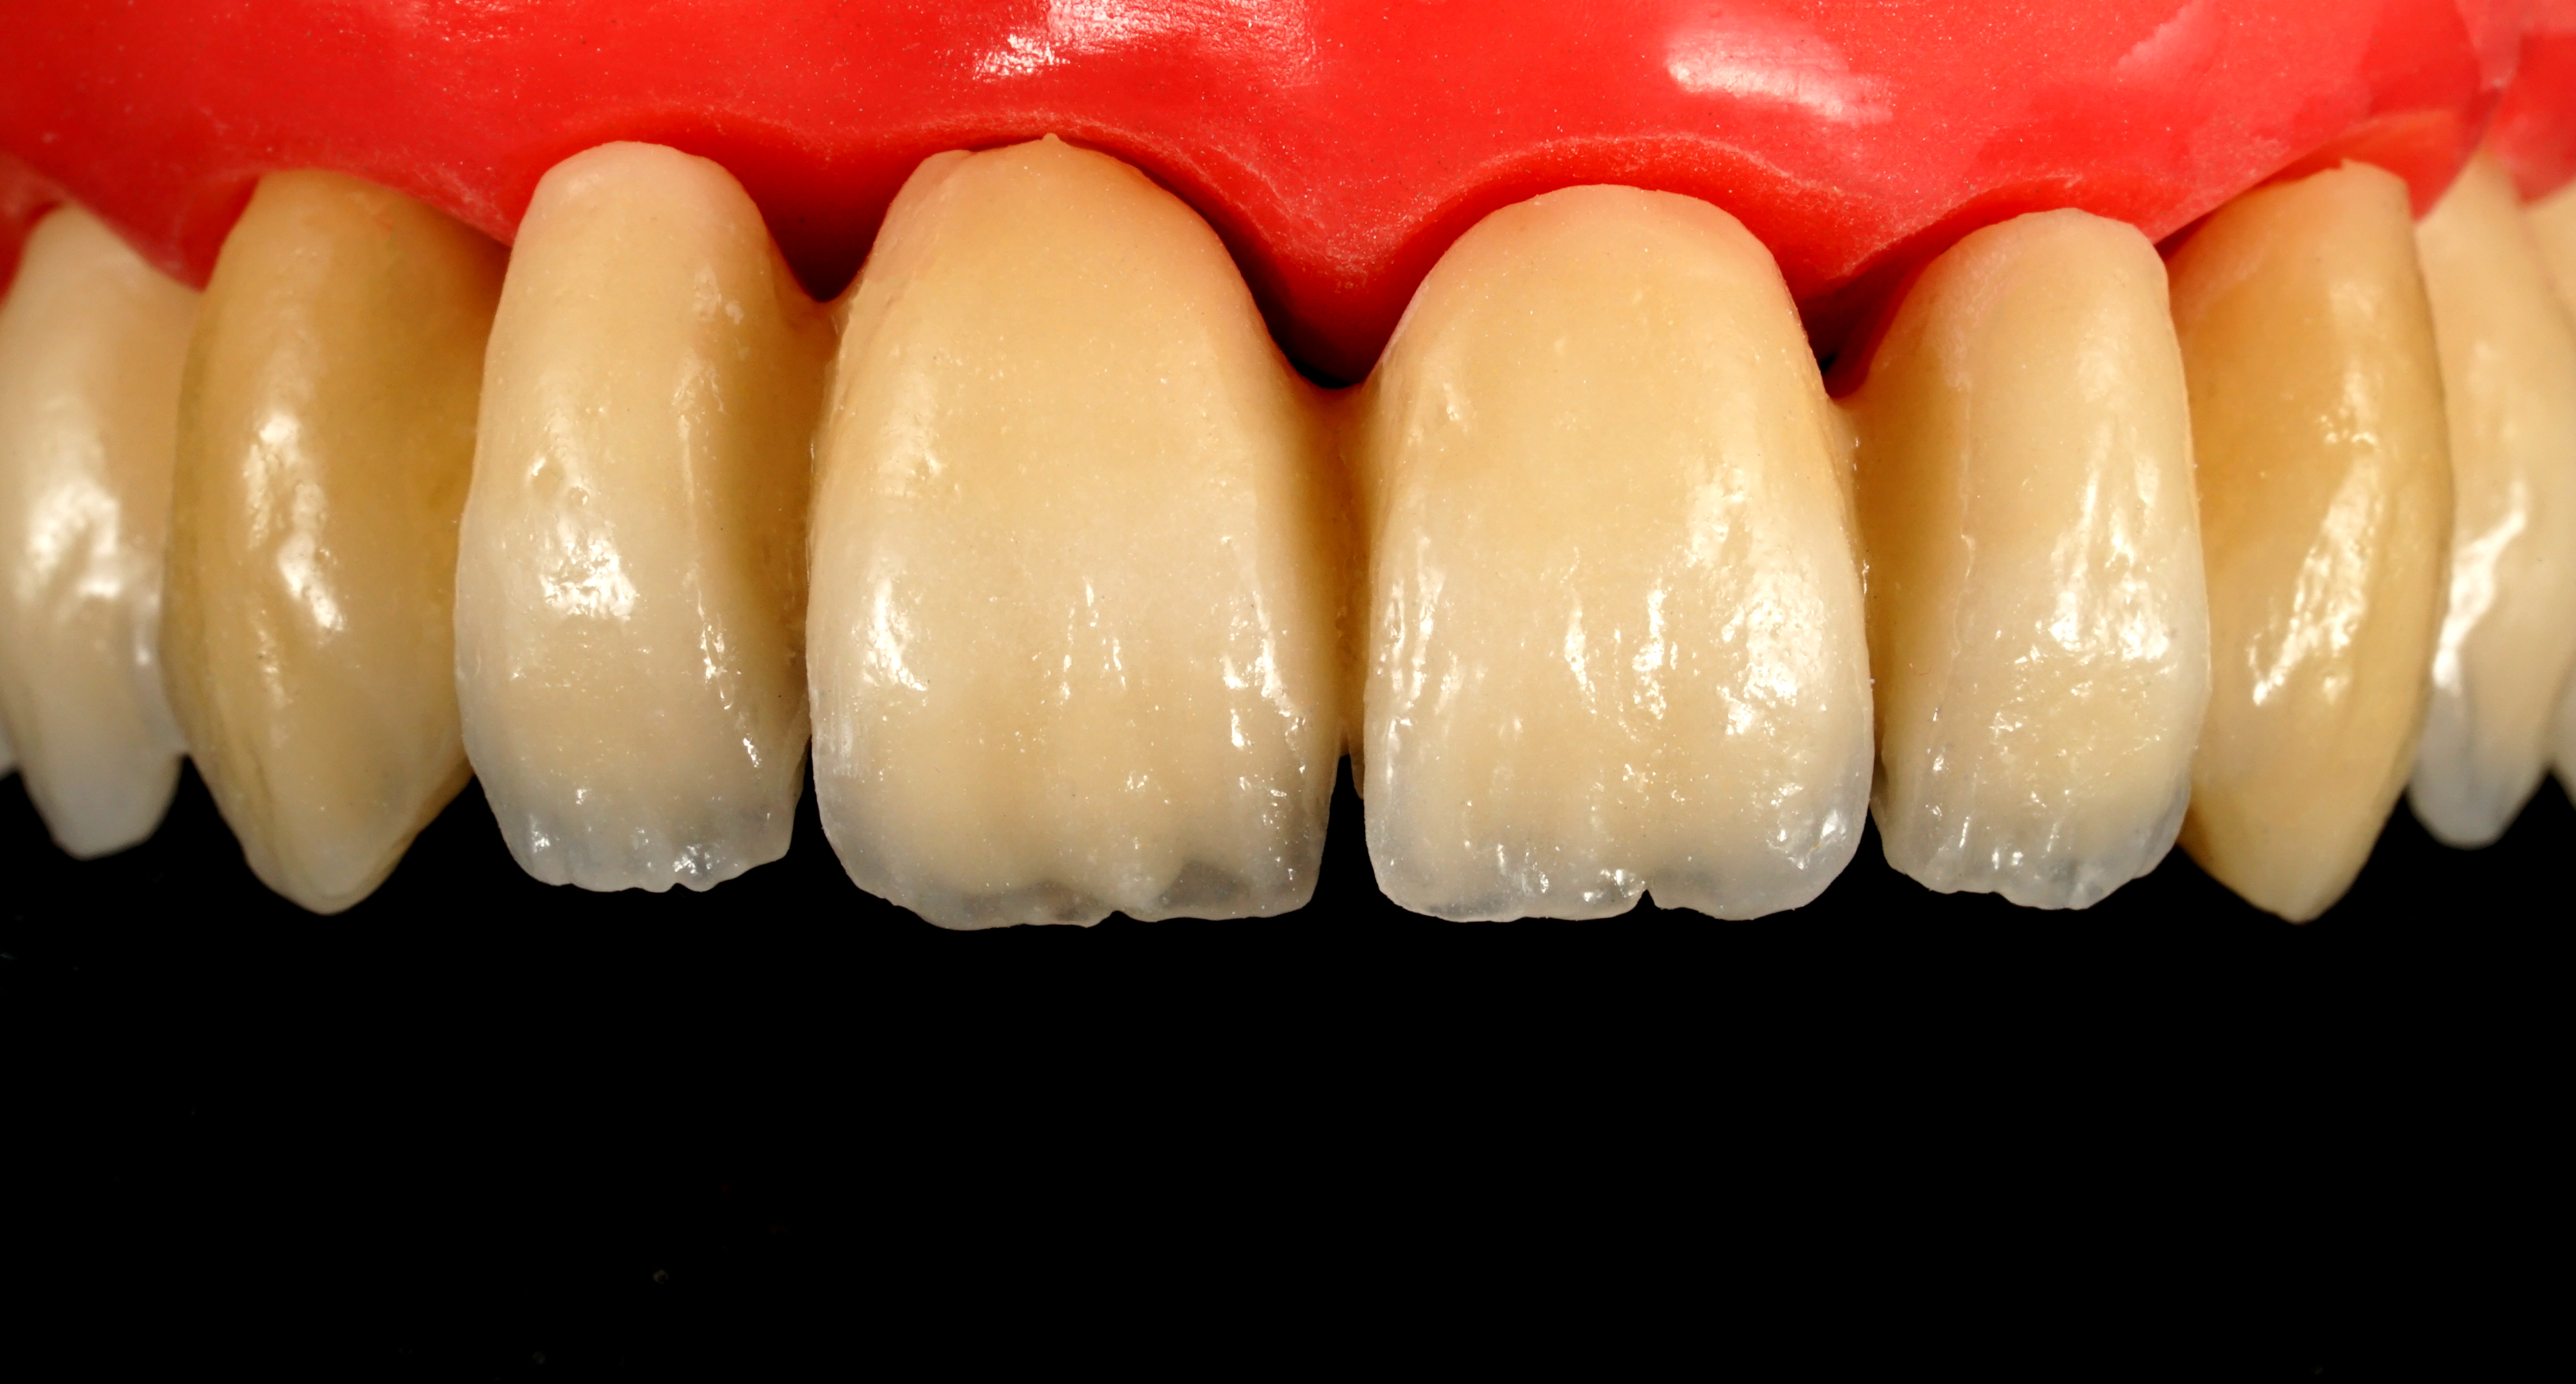

La parte di ceramizzazione è stata affidata ad una solida certezza interna al nostro laboratorio DentOne: Fabrizio Pasini, il quale ha espresso il suo sublime gusto estetico stratificando ad arte una base in CoCr con ceramica Shofu (Fig. 17, 18, 19, 20, 21).

Fig. 17. Stratificazione estetica multi-massa effettuata da Fabrizio Pasini